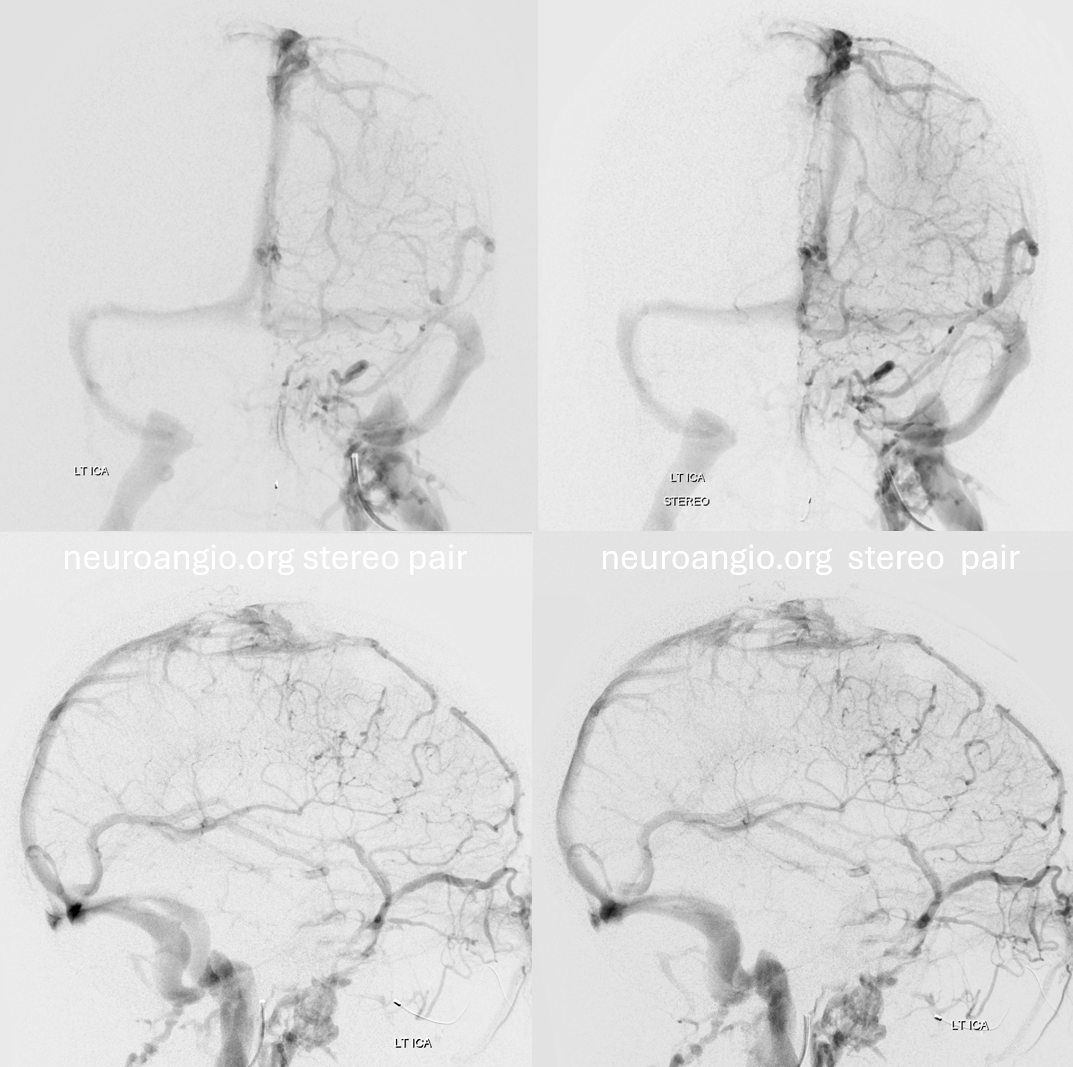

Later on… right side is good

Left side is bad — can you see it?

Later phase of bad